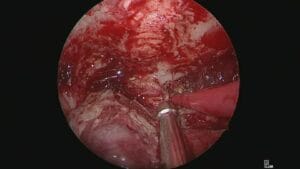

Estapedotomía: ventana oval estrecha y dehiscencia del VII par

El Dr. Robert Vincent realiza una estapedotomía compleja en una ventana oval extremadamente estrecha, asociada a una dehiscencia severa del nervio facial.